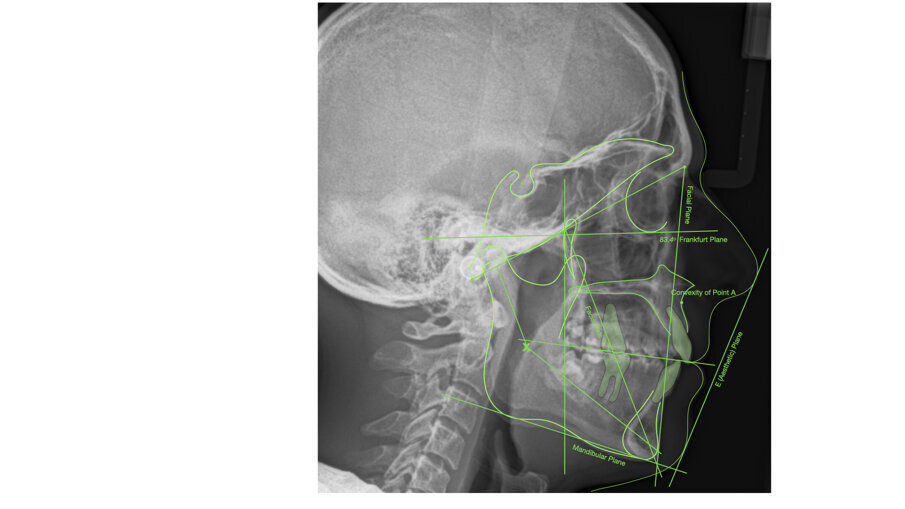

Dal punto di vista parodontale il paziente ha mostrato una buona attitudine all’igiene orale, ma l’affollamento degli incisivi mandibolari ha reso difficile la pulizia in quell’area, causando un accumulo di placca e un’infiammazione gengivale localizzata. La radiografia panoramica ha rivelato la presenza dei terzi molari mandibolari e ha confermato l’assenza dell’incisivo centrale mandibolare destro (Fig. 10). L’analisi cefalometrica ha evidenziato una malocclusione scheletrica di Classe II (convessità del Punto A: 4,9 mm), una posizione leggermente retrusa del mento (profondità facciale: 78,1°) e una tendenza scheletrica al morso aperto (altezza facciale inferiore: 53,19°; asse facciale: 80,58°; Fig. 9). Gli incisivi mandibolari erano inclinati lingualmente (Li-APog: 9,3°) e retrusi (Li-APog: 1,55 mm), con un angolo interincisivo aumentato di 142,9°.